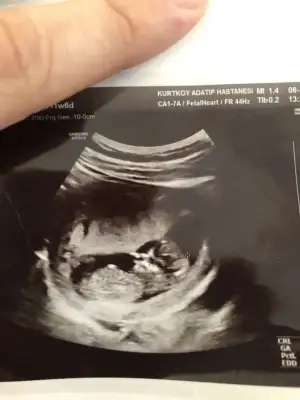

Merhaba arkadaşlar 11 haftalık ultrason görüntüsü, çookk merak ediyorum yorumlayabilir misiniz :))

• ultrason.webp

ultrason.webp

21,3 KB · Görüntüleme: 108